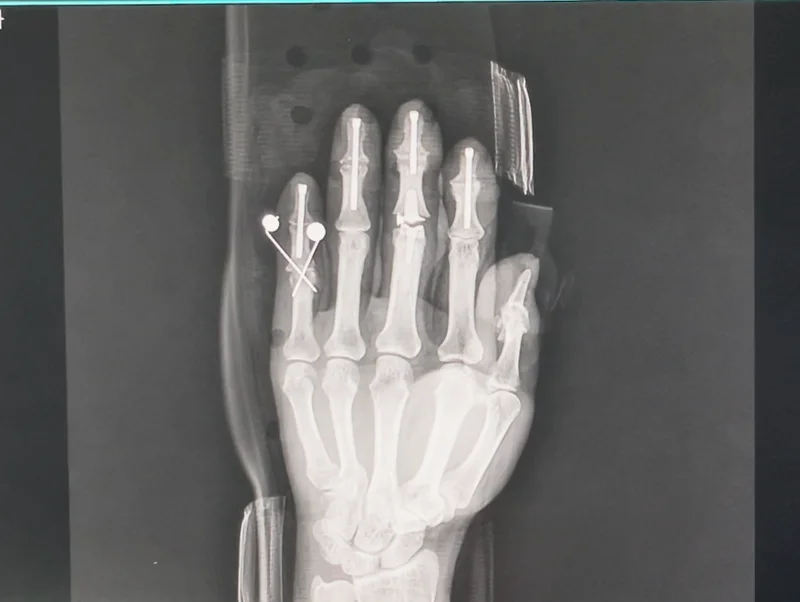

右側の写真は手術から2日が経過した後に

撮影したX-ray写真です。

手術前に撮った写真と比較してみると

指がしっかりと正しく伸びているのが

分かるかと思います。